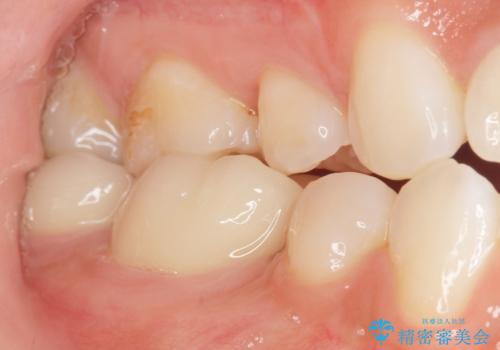

矯正せずに隙間を閉じることができ、ご満足頂けました。

セラミッククラウンの審美的な仕上がりと咬み心地に喜んで下さいました。

クラウンの種類:オールセラミッククラウン スタンダード